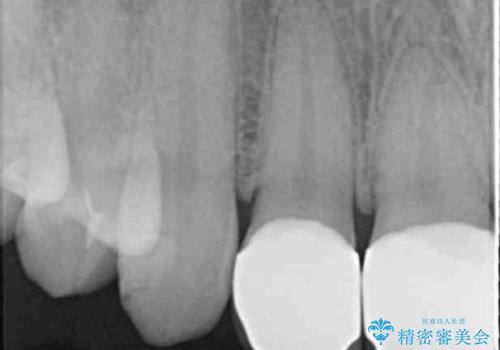

- 保険治療のプラスチックでつぎはぎの歯をセラミックにし、一緒に前歯の並びもきれいにしたいとのご希望でした。

特に裏側のつぎはぎ、二次う蝕(治したところの境目からの虫歯)が多く、審美目的だけでなく、虫歯の治療としても意味があったと思います。

神経を温存するようにあまり削らないように治療しました。

- 51.7万円(ジルコニアクラウンスタンダード 10万円x4本、仮歯1万円x4本 オフィスホワイトニングエクセレント 3万円x1回)費用は治療当時の料金となります